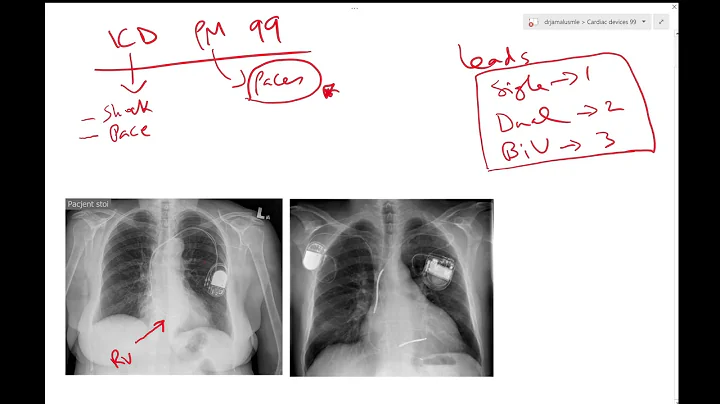

Learn The Difference Between A Defibrillator And Pacemaker

Dr. Eli Beaty, a cardiologist at Wake Forest Baptist Health, discusses how an EP specialist can help control electrical impulses of ...